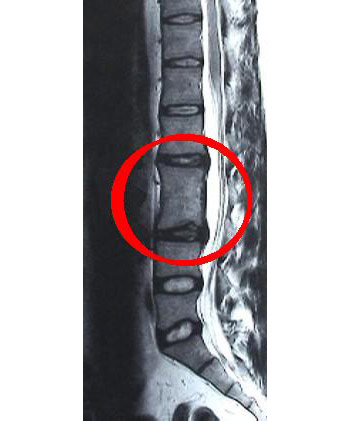

Врожденный кифоз (болезнь Шейермана – Мау) связан с расположением рядом клиновидних позвонков в грудном отделе позвоночника, что вызывает формирование вертебрального кифоза. Болезнь требует хирургической коррекции при выраженном нарушении осанки с наличием горба.